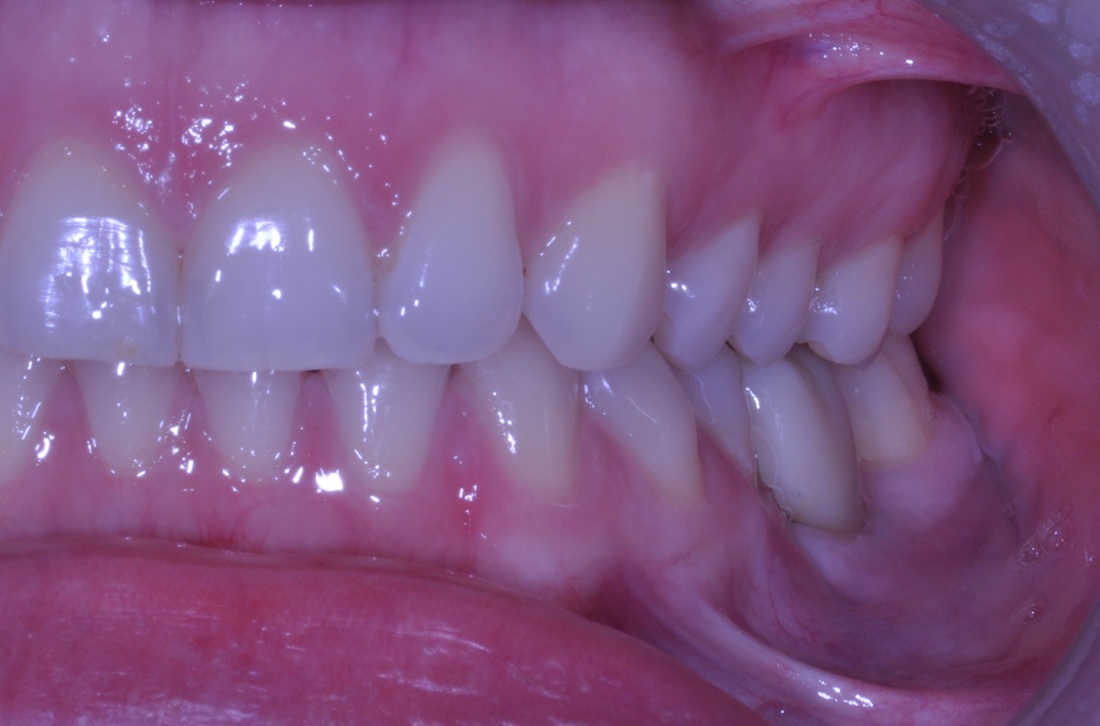

ANTERIOR IMPLANT

A graduate student came to our DENTOLOGY practice with a broken upper front tooth. Dr. Andrews recommended to replace it with a dental implant. Due to high smile line and anatomy of the area, this type of cases is considered to be one of the most challenging for a dentist to treat.

Without any incisions, Dr. Andrews removed the broken root and placed an implant along with a bone graft during the same surgery. Immediately, a temporary crown was attached to two other front upper teeth to form the ideal shape for the soft tissue profile. A few months later, 3D Intraoral scan was taken and Dr. Andrews used Virtual Prosthodontics (CAD) and Reverse Restorative Rehabilitation Protocol to design Full Contour Zirconia (FCZ) screw-retained Implant Crown.

Then the crown was milled (CAM) and sintered by a specialized Milling Center. Once it had been received, the FCZ restoration had been custom shaded and glazed at DENTOLOGY in-house lab. During the patient’s next and final visit, all-ceramic crown was delivered via screw-retained fashion to prevent any complications associated with cement retention under the gum margin (the most common reason for implant failures in intraorally cemented cases).